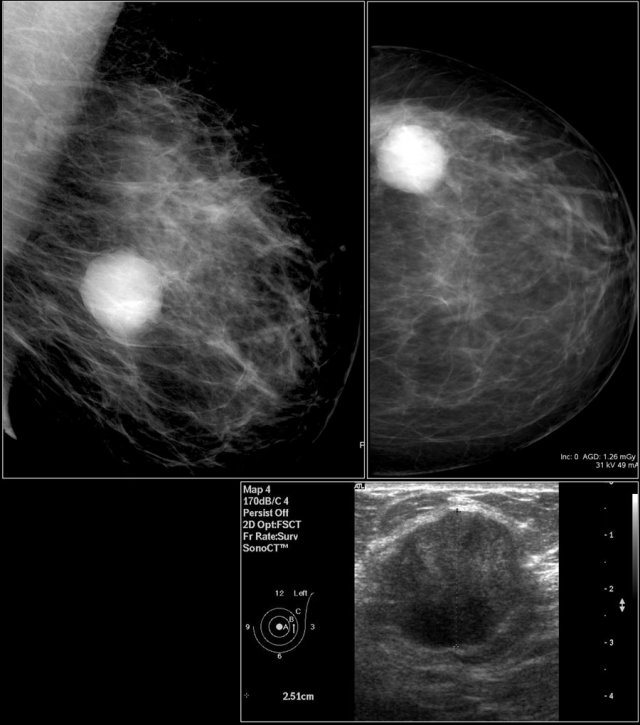

First study the images and describe the findings.

Then continue reading.

The findings are:

• Mass with irregular shape.

• Spiculated margin.

• High density.

• Ultrasound also shows irregular shape with indistinct margin.

This mass is categorized as BI-RADS 5.